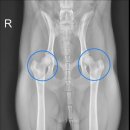

• 배방동물병원 | 배방 언제나외과동물병원 "4살 강아지 양측 대퇴골두절골술(FHNO) 후기"

병원. 언제나외과동물병원입니다. ​ 오늘은 솜이의 대퇴골두절골술(FHNO)수술 후기를 전해드립니다. ​ "대퇴골이란?" 대퇴골은 쉽게 말해 허벅지뼈 입니다. 윗부분...대한 자세한 설명은 아래 글에서 확인 할 수 있습니다^^ [언제나외과동물병원] 강아지 고관절질환, 종류와 치료방법은 무엇일까? 안녕하세요! 언제나외과...

• 배방동물병원 | 아산 탕정 배방 언제나외과동물병원 "5살 강아지 양측 슬개골탈구, 양측 대퇴골두절골술(FHNO) 후기"

​ 안녕하세요. 아산 탕정 천안의 대표 외과동물병원. 언제나외과동물병원입니다. ​ 오늘은 콩이의 슬개골 탈구 수술과 대퇴골두절골술 후기를 전해드립니다. "슬개골이란? " 무릎 관절에 위치하고 있는 손톱사이즈의 아몬드모양의 뼈를 슬개골이라고 합니다. 슬개골은 무릎관절에서 위아래로 움직이면서 운동하여 안정적인...